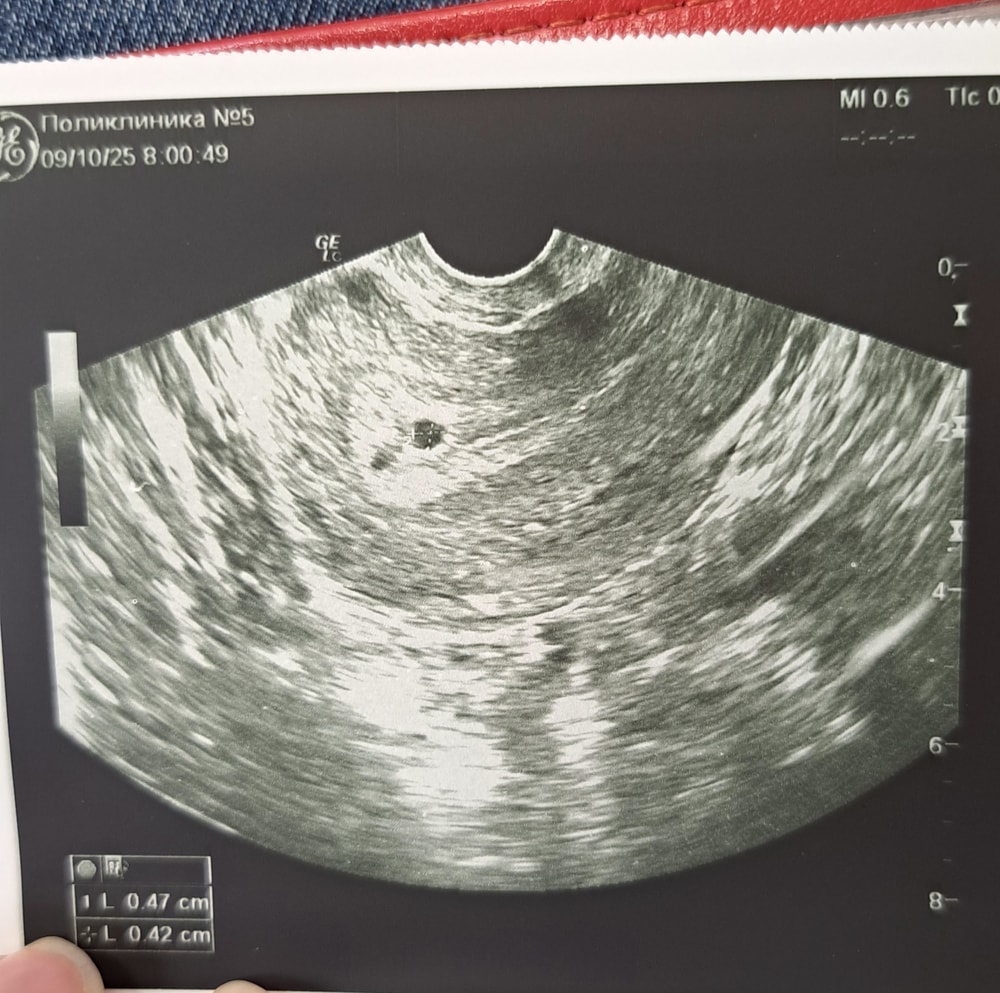

Обследования, узи, анализыОписание забыла сфоткать. Но во всяком случае фоточка есть) ПЯ в матке)) жт визуализируется. эмбрион пока не видно, такое узи мне делали в ведомственной поликлинике, а вот 17 я иду уже в женскую консультацию и там уже будет все ясно. При каком хгч видно эмбрион?

У меня увидели когда хгч был 1000+

Вот примерно такая же картинка была как у вас на фото 😍

Многие пишут что от 1000, но у меня при 2600+ не видно еще было эмбриона и ЖМ.

Элина, Желтое тело, наверное имеете ввиду? У меня оно тоже было. А вот желточного мешочка не было, он вроде в матке сразу должен быть с эмбрионом(кольцо с бриллиантом). Но я еще дилетант в этих беременных делах, могу ошибаться:)